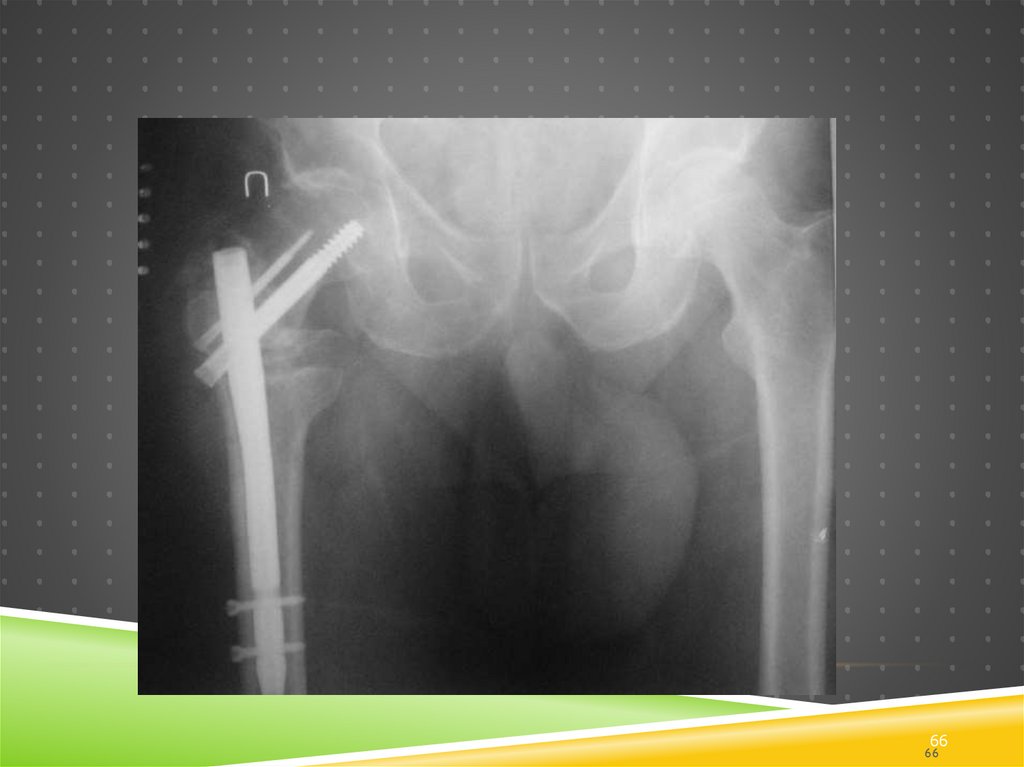

Через 2 мес.

Post-op